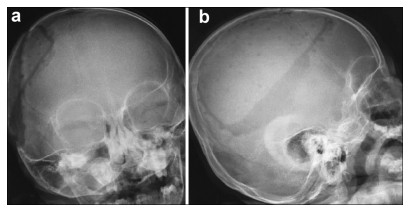

All 13 patients were followed up for 1 year,and CT scan or radiographic imaging was taken every 3 months. Postoperative radiography taken at 1 year showed cracks on the biomimetic bone in one case (Figure 2),while no instability occurred. The imaging results of the other cases showed symmetric skull shapes and smaller bone gaps. Different cases of cranioplasty show well appearances in postoperative cranial VRT reconstruction (Figures 3a-3f). The temporal muscle had free movement (Figures 3c-3f). The value of the CT scan changed from 750 ± 50 HU to 875 ± 50 HU (Max 925) in 1 year. The cancellous bone/compact bone differentiation appeared in two cases (Figures 4a and 4b).

| Figure 2 Postoperative head X-ray image of 1 case reveals satisfactory fixation of the biomimetic bone, good radian, connected to the coronal suture without crack. Figure 2b Postoperative head X-ray image of the same case 1 year later shows density of the biomimetic bone close to the normal bone, but visible cracks can be observed, consistent with child’s normal skull development. |

In one baby who was no more than 2 years old, the postoperative head X-ray and volume rendering technique (VRT) imaging after 1 year showed visible cracks. We assume that the brain grew faster than the speed of bonding osteogenesis,causing the biomimetic bone to crack at the place of the coronal suture (Figure 2). However,negligence by parents cannot be ruled out. The following are the limitations of this study: this study sample size is small,follow-up time is short,and clinical curative effect needs further research.